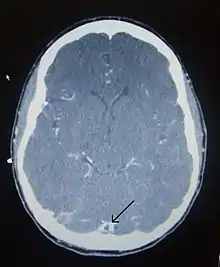

There are various neuroimaging investigations that may detect cerebral sinus thrombosis. Cerebral edema and venous infarction may be apparent on any modality, but for the detection of the thrombus itself, the most commonly used tests are computed tomography (CT) and magnetic resonance imaging (MRI), both using various types of radiocontrast to perform a venogram and visualise the veins around the brain.[2]

Computed tomography, with radiocontrast in the venous phase (CT venography or CTV), has a detection rate that in some regards exceeds that of MRI. The test involves injection into a vein (usually in the arm) of a radioopaque substance, and time is allowed for the bloodstream to carry it to the cerebral veins – at which point the scan is performed. It has a sensitivity of 75–100% (it detects 75–100% of all clots present), and a specificity of 81–100% (it would be incorrectly positive in 0–19%). In the first two weeks, the "empty delta sign" may be observed (in later stages, this sign may disappear).[8] The empty delta sign is characterized by enhancement of the dural wall without intra-sinus enhancement.[4]